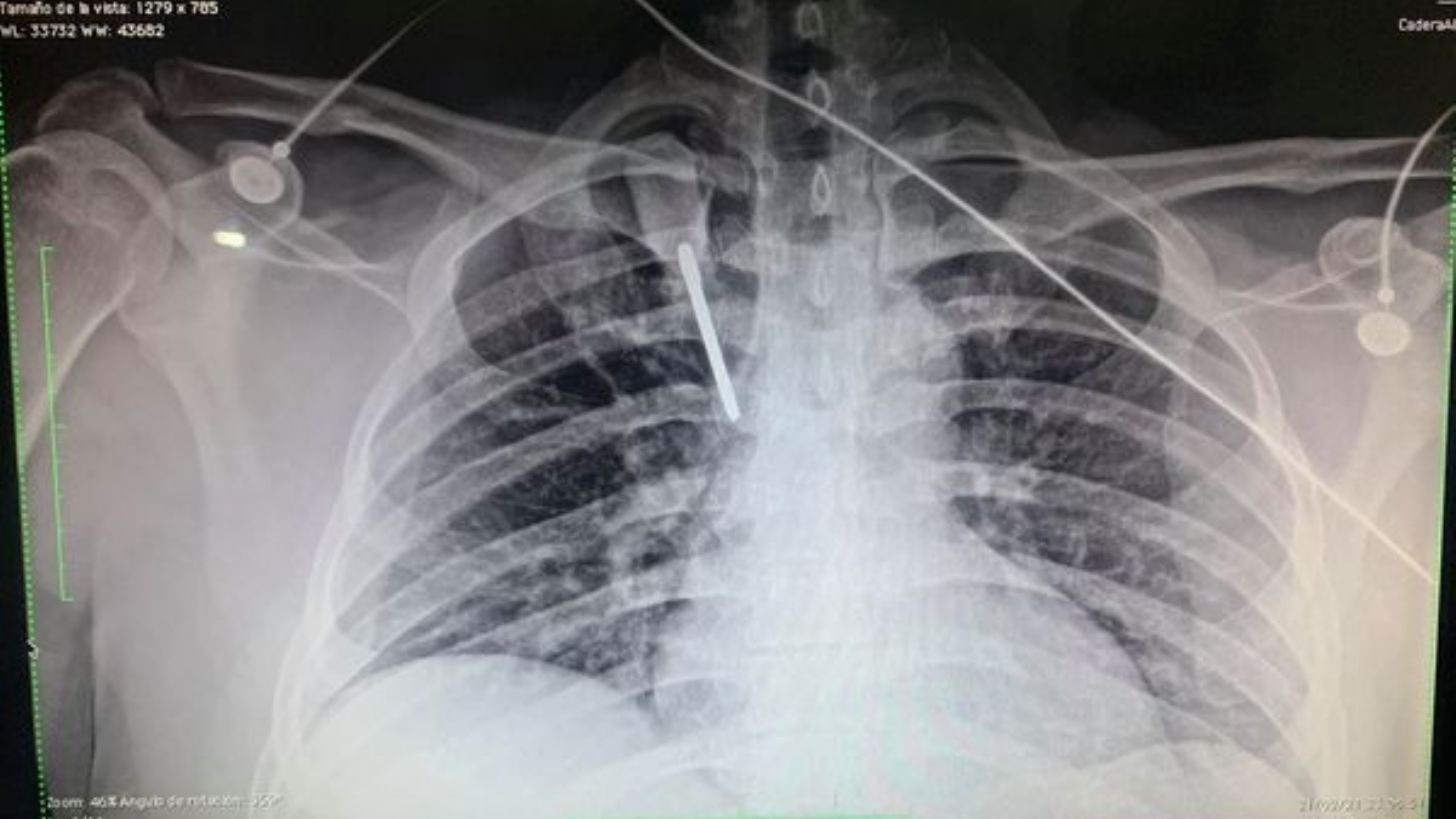

Junto a la publicación, compartió unas fuertes fotografías en las que se ven los rayos equis que muestran la herramienta usada como arma y a él, quien estuvo en un estado de salud crítico.